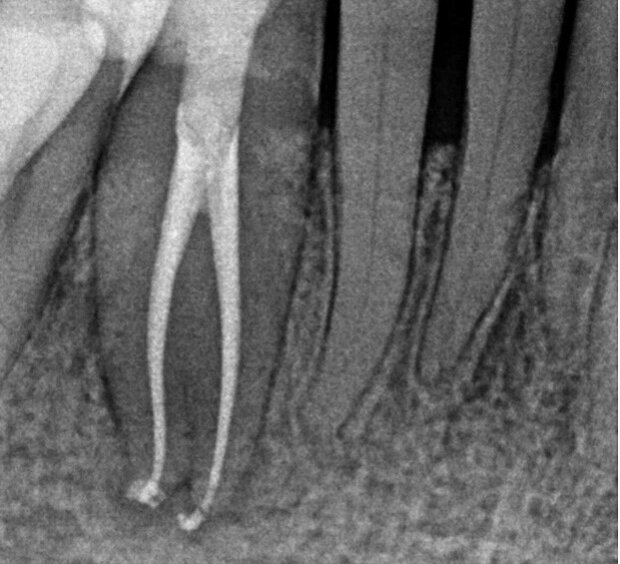

Quando la carie o un trauma arrivano ad esporre il tessuto pulsare interno del dente (composto da vasi sanguigni e nervi), i batteri che invadono i tessuti causano un'infiammazione acuta chiamata "pulpite" che, se non trattata, si cronicizza portando alla necrosi della polpa. I prodotti di decomposizione batterica, dalla camera pulpare migrano verso l'apice del dente fino a raggiungere il forame apicale (un foro che mette in comunicazione l'interno del dente con l'osso circostante) e da qui raggiungono la porzione di osso circostante le radici scatenando quella che viene definita "parodontite apicale" che, se non curata, porta alla formazione di ascessi, granulomi o cisti.

Per eliminare il dolore causato dall'infiammazione pulpare e far guarire le lesioni apicali, si ricorre alla terapia endodontica che prevede le seguenti fasi (raffigurate nell'immagine sottostante)

Otturazione tridimensionale dei canali con guttaperca per la formazione di un sigillo apicale